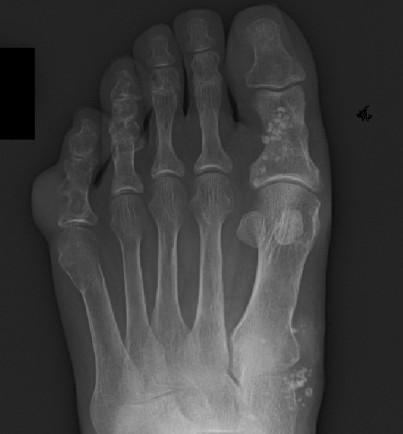

![Mafucci syndroom (click on photo to enlarge) [source: www.huidziekten.nl] Mafucci syndroom](../../../images/mafucci-syndroom-3z.jpg) |

| Maffucci

syndroom |

Foto's: Miki Tanioka - Mafucci syndrome -

www.intechopen.com (Creative Commons License

3.0).